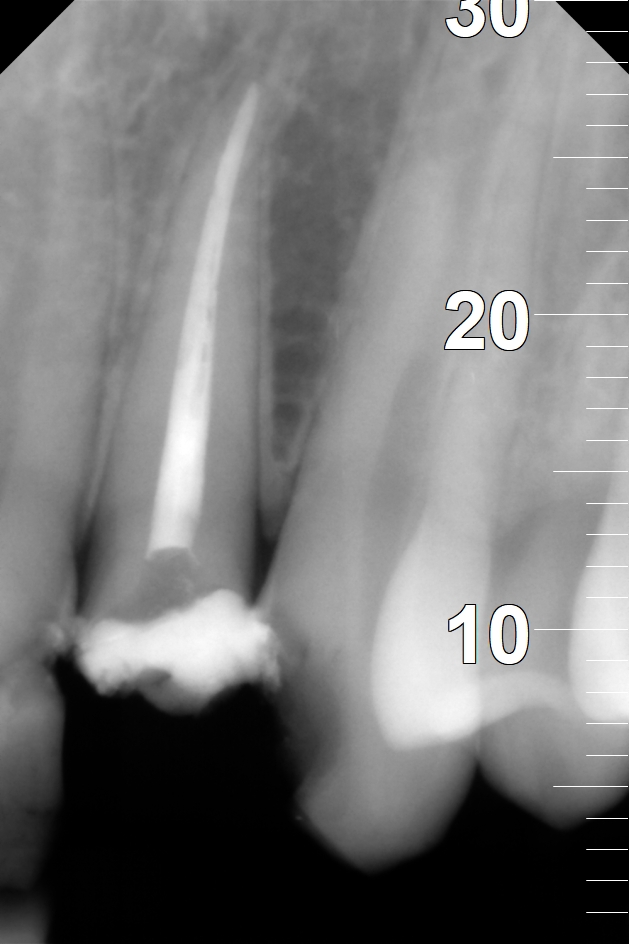

Na nasledujúcich RTG snímkoch sú dobre viditeľné biele výplne ošetrených koreňových kanálikov. Biela farba na snímkoch je spôsobená tým, že výplňový materiál je zámerne RTG kontrastný, aby bolo ľahko možné identifikovať výplne koreňových kanálikov.

Zaplnený koreň zuba číslo 22 pred rekonštrukciou korunky.